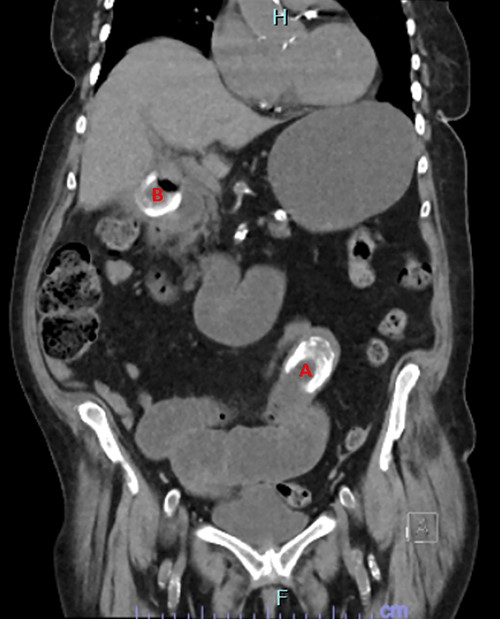

Her investigations found mildly elevated inflammatory markers, with a white cell count of 11.7 and a C-reactive protein of 75. A computed tomography (CT) abdomen and pelvis was performed which found a high-grade bowel obstruction secondary to a large gallstone lodged in the distal jejunum (Fig. 1). A second gallstone was identified located in the gallbladder, with the possibility raised that the gallstone was partially traversing the duodenal wall.

CT image showing obstructing gallstone (A) and gallstone in cholecystoduodenal fistula traversing duodenal wall (B).